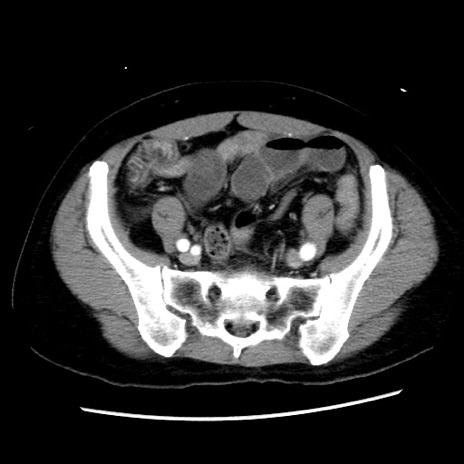

症例10(横断像)

【症例】 50歳代女性

【主訴】 腹痛

【現病歴】前日生レバーを食べた。今朝に排便あり。 昼前に突然発症の腹痛を生じ、当院救急外来を受診した。

【既往歴】 子宮筋腫にてで子宮全摘後

【身体所見】 意識清明、腹部:平坦、軟、下腹部やや左を中心に圧痛・反跳痛あり、筋性防御あり

【データ】WBC 7800、CRP 0.07